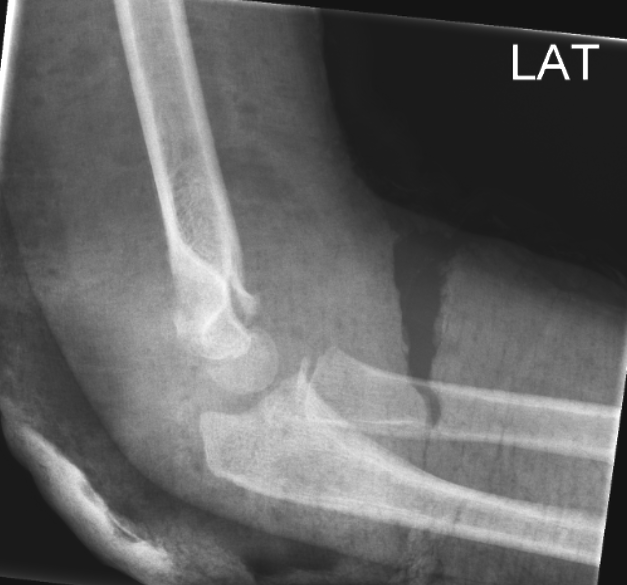

Gartland type III Total dislocation

Gartland type III

Svære frakturer kan godt tåle at vente til næste dag, hvis der ikke er kar eller nervepåvirkning. Anlæg en skinne, indlæg og hold fastende til næste morgen. Kontroller puls og nerve funktion.

Osteosyntese med K-tråd brug 1,6 mm

Åben adgang medialt aht at nervus ulnaris ikke fanges af K-tråden.

Ved 2 laterale K-tråde kan de være divergerende, god stabilitet opnås med 2 krydsede K-tråde fra hver side, hvor de ikke krydser svarende til frakturen.

Buk K-trådene og lad dem være udenfor huden.

K-trådene fjernes i GA på DKC. Untagelsesvis i amb uden anæstesi med EMLA.

Gips 3 uger.